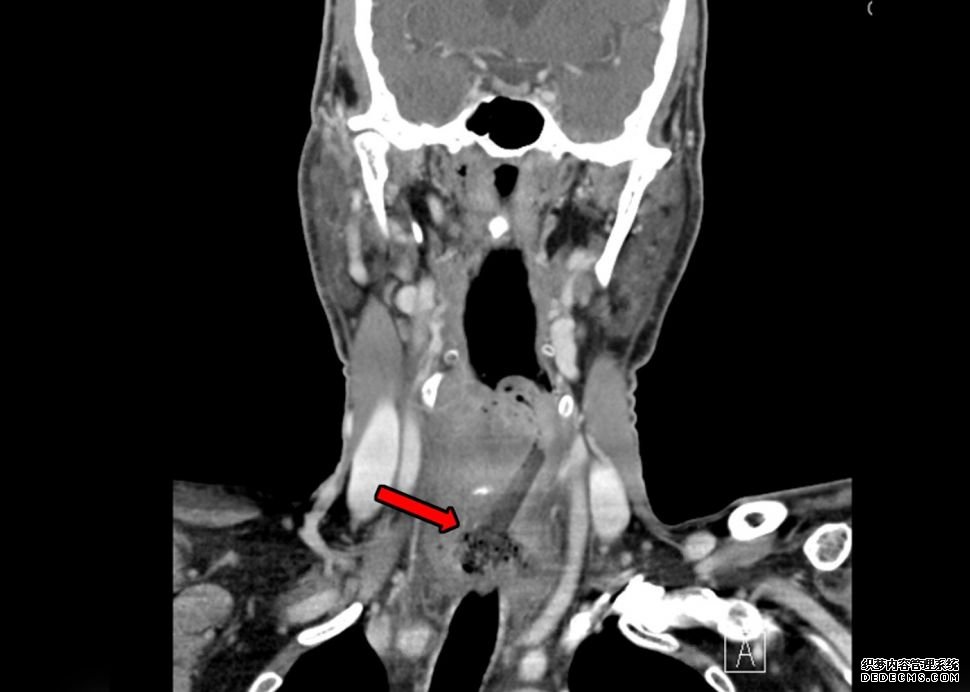

一名男子吃母亲节纸杯蛋糕吃得太快,不小心吞下了2英寸(5厘米)的蛋糕。上图,CT扫描显示,如图中红色箭头所示,上衣卡在男子的食道里。

但在约翰霍普金斯大学,医生们要求做CT扫描,结果显示他的食道里有“一个5厘米长的异物”,他们写道。